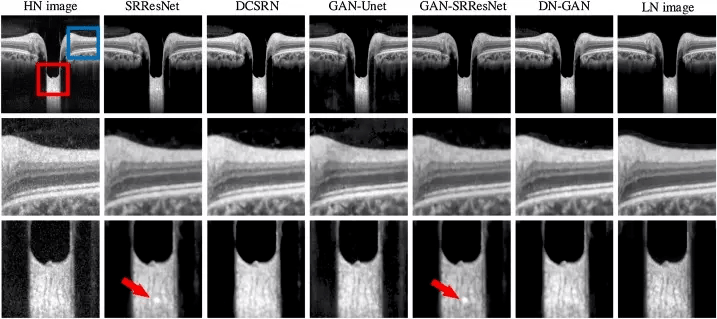

Denoising — removal of all kinds of noise from the data. For example, removing statistical noise from x-ray images fits medical needs, which will be described in our use cases.

Figure 7. Removing noise from tomography images using GAN (source)